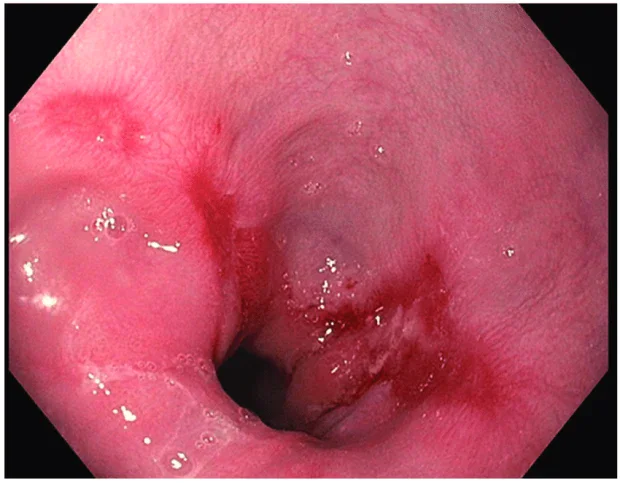

- ендоскопия: с високо информативно значение са резултатите от ендоскопското изследване (горна ендоскопия), при което се визуализират промените по хода на лигавицата на хранопровода

Изображение: researchgate.net/Creative Commons Attribution 4.0 International